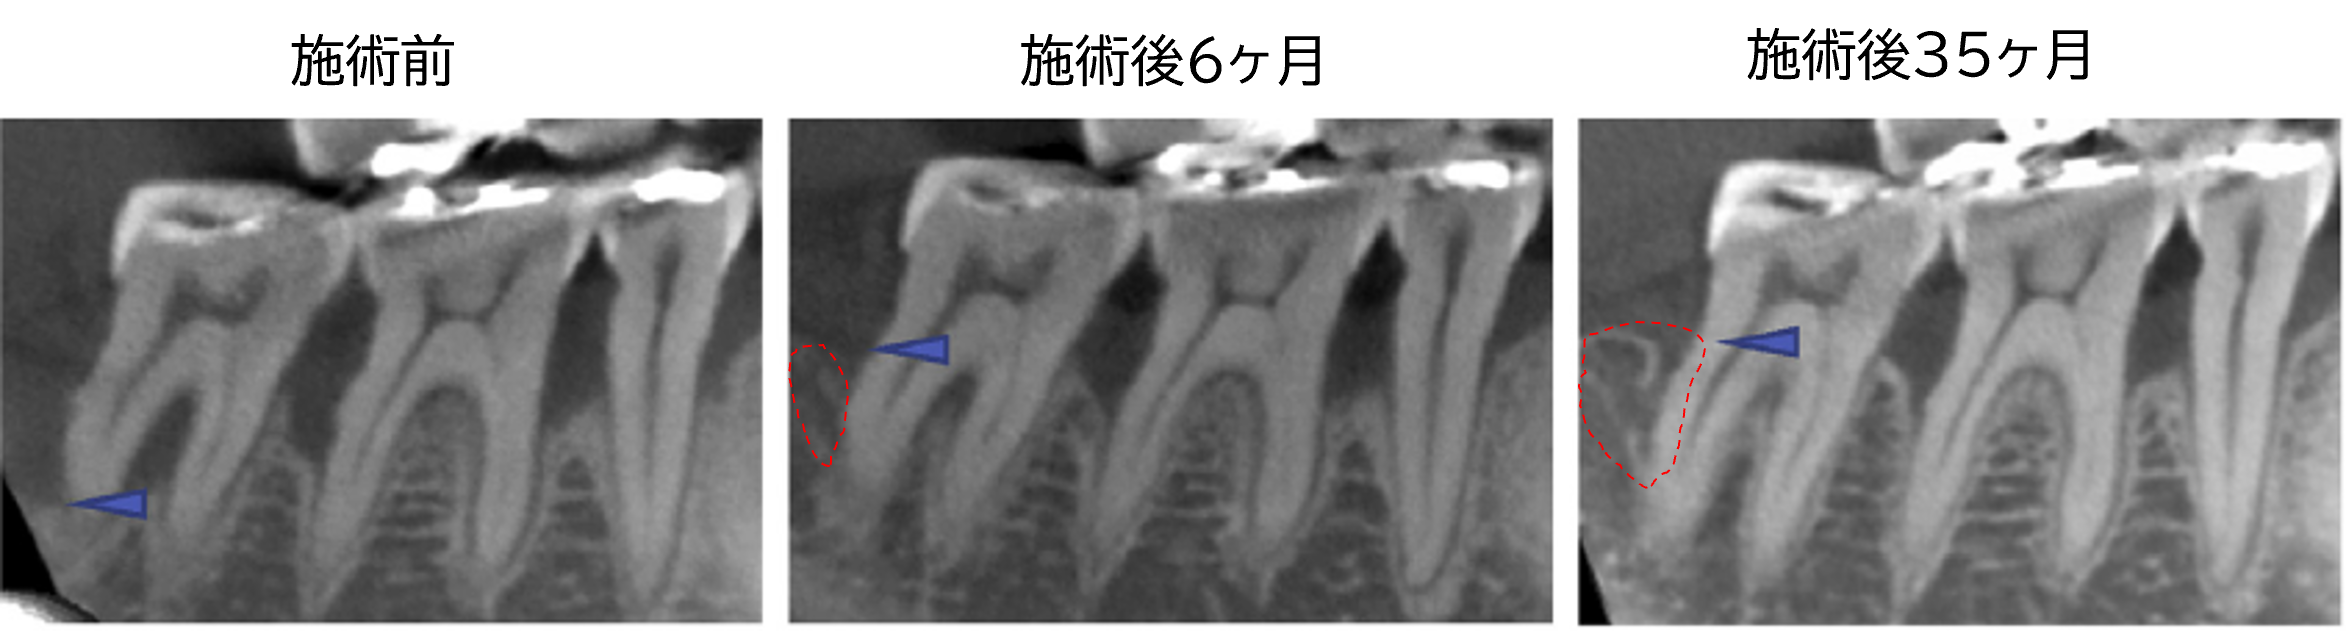

症例B|63歳女性

左下の小臼歯から臼歯にかけて広範囲に骨欠損があり、歯の根元が分かれている部分(分岐部)にも病変が及んでいました。欠損は第二大臼歯の根の先端まで達していましたが、歯根膜細胞シートの移植により、6ヶ月後には分岐部が閉鎖し、骨の高さは5.89mm増加。さらに35ヶ月後には骨の状態が安定していることが確認されました。